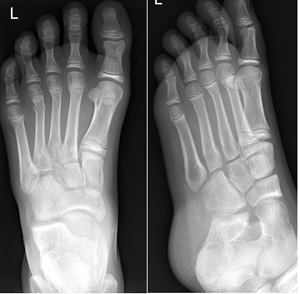

Avulsion fracture at the base of the fifth metatarsal (insertion of peroneus brevis)

Fracture of base of 5th metatarsal follow inversion injury

- CAM boot weight bearing as tolerated with Fracture Clinic follow up in 1 week.

- It is important to differentiate avulsion fractures of the base of the fifth metatarsal with Jones fractures which involve the 4th and 5th inter-metatarsal joint.

- These intra-articular fractures are managed in a below knee backslab non weight bearing with crutches and Fracture clinic follow-up in 1 week.